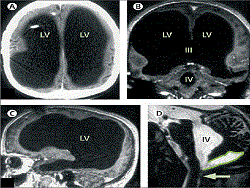

Мужчину еще в детстве лечили от гидроцефалии (когда в головном мозге скапливается лишняя жидкость). Лечение прошло успешно, однако в возрасте 44-х лет француз обратился к врачам с жалобой на боли в ноге, которые ему постоянно докучали. В самой конечности ничего найти не смогли, поэтому врач назначил комплексное исследование пациента, включая область головного мозга. Когда провели МРТ, то врачи были крайне удивлены тем, что серое вещество француза практически отсутствует в черепной коробке, однако это никоим образом не сказывается на самом мужчине.